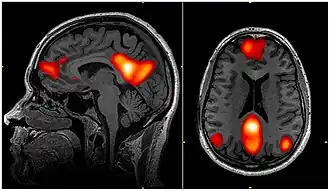

fMRI scan showing regions of the default mode network; the dorsal medial prefrontal cortex, the posterior cingulate cortex, the precuneus and the angular gyrus